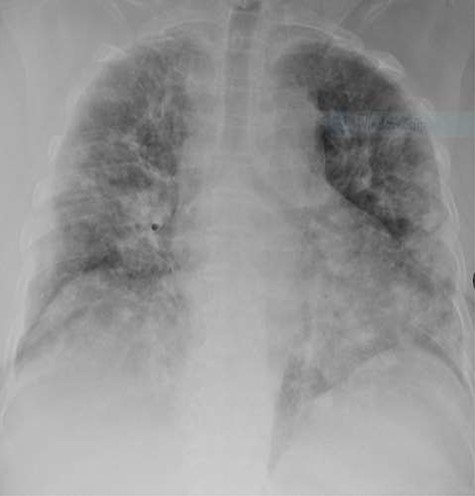

Laboratory investigations were within normal ranges except for D-dimer, which was high (Table 1). Chest X-ray showed bilateral homogeneous opacification (Fig. 1).